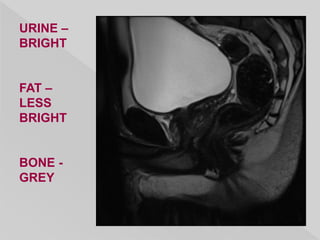

URINE –

DARK

FAT –

BRIGHT

BONE -

GREY

MALE PELVIS – AXIAL T1WI – PROSTATE DARK

LESS